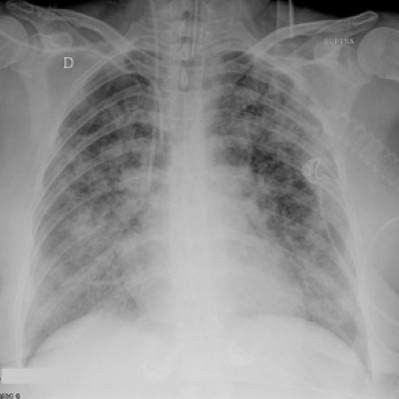

This is a chest x ray of a patient with ARDS

Any black areas are normal lung tissue.

The fluffy white areas are the congestion due to fluid collecting in the lung and air sacs.

These are responsible for preventing oxygen to get into the lungs and then out to the vital organs.